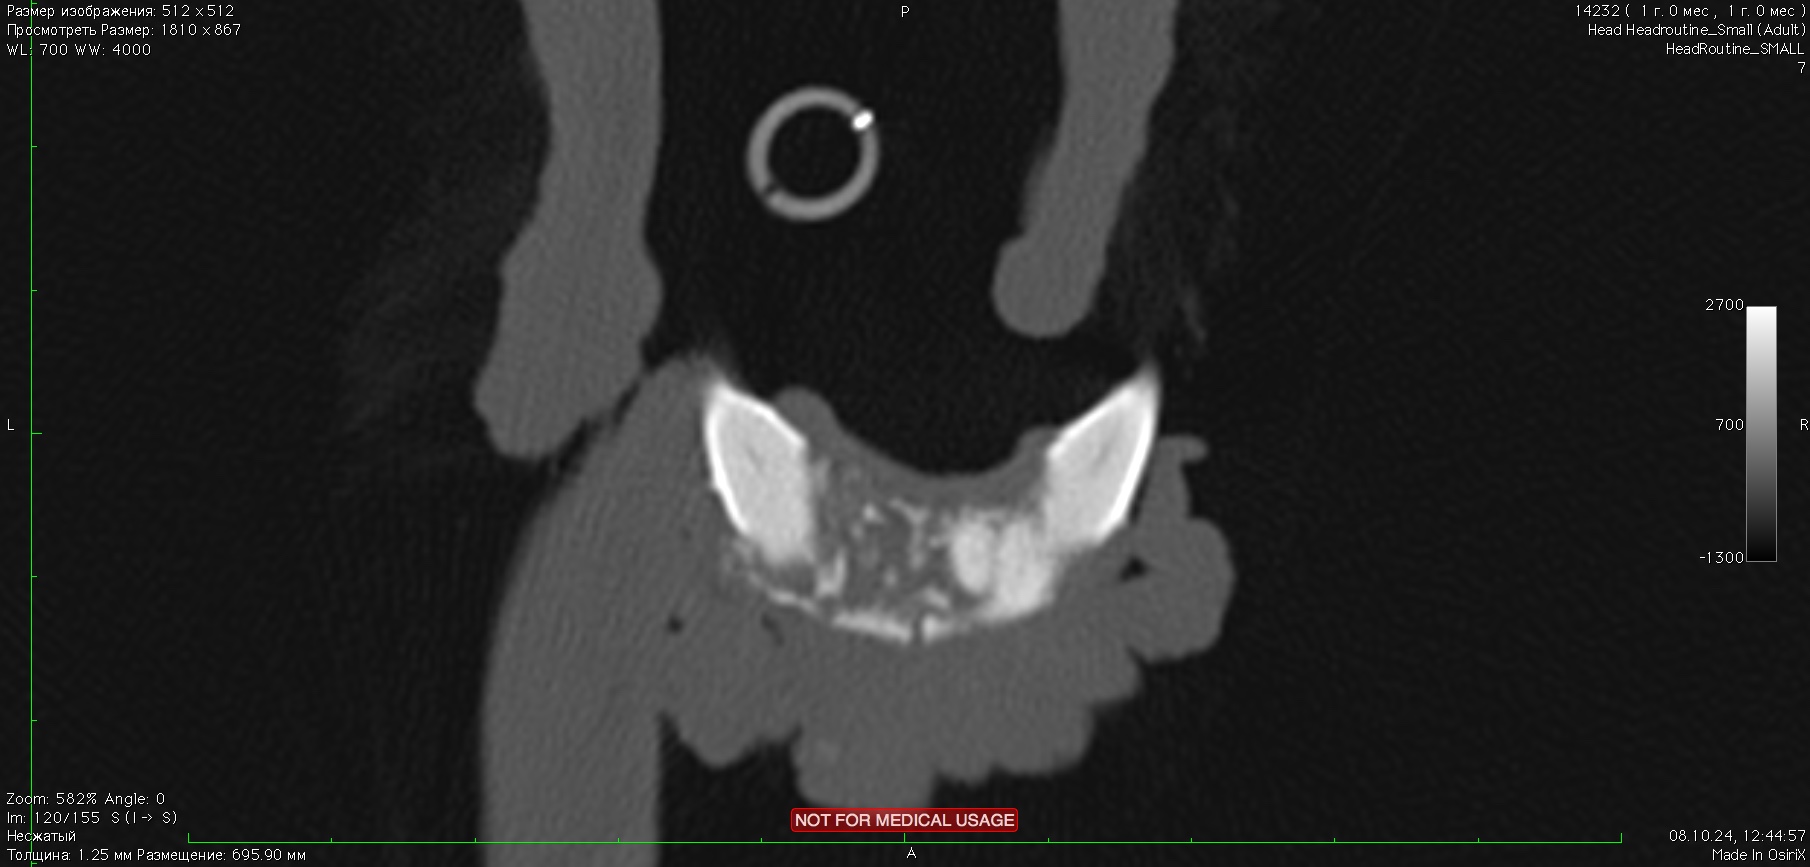

- 08.10.2024 обращение с жалобой на растущее новообразование на нижней челюсти. Осмотр выявил признаки новообразования размером 16 x 12 мм на ростральной части нижней челюсти справа, поражая клык и область резцов. (изб. 8). Проведена частичная ростральная мандибулэктомия. Морфологический диагноз – амелобластома, границы резекции содержат опухолевый рост.

Изображение 8. Резцы нижней челюсти 301, 302, 303 и 401 отсутствуют. Между резцом 402 и клыком 304 наблюдается лизис и периостальная реакция нижней челюсти. На этом уровне также выявляется мягкотканевое образование размером 16 x 12 мм с умеренным кровотоком и множественными кальцификатами.